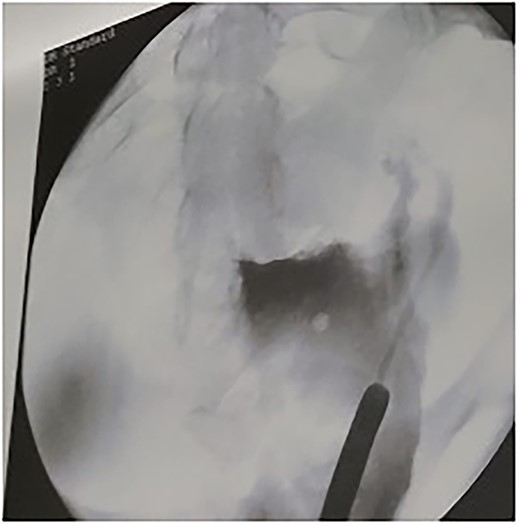

Under spinal anesthesia, supine position, the patient underwent laparotomy with a transverse skin incision and midline incision of the fascia. Exploration confirmed the pre-operative diagnosis. The retroperitoneal space was entered, and ureters were identified bilaterally. A window was opened (broad ligament) at the level of the uterine artery to ligate uterine arteries using ligasure, ureterolysis was done and both ureters were skeletonised down to the ureteric tunnel (as in radical hysterectomy). The uterosacral ligament and cardinal ligament were ligated using ligasure, at the level of the cervico-vagina junction. An anterior colpotomy was done after the dissection of the bladder and creation of the bladder flap, and the anterior colpotomy was extended laterally from each side by using ligasure with careful attention to keep the ureters away. The circumcision of the cervix was completed by using Heaney clamps at the vaginal angles. The uterus was mobilised along with the cervix and the myoma and completely separated from the vagina (Fig. 1). At this point, cautery was used to amputate the cervix with careful attention to maintain the integrity of the infundibulo-pelvic ligament (Fig. 1). The uterus was sutured to the vagina with the box technique, where the posterior aspect of the vagina and cervix was sutured, followed by the lateral and anterior wall. After that, one proline permanent suture was used as a cerclage, used to support the uterus for future pregnancy (Figs 2 and 3).

The cerclage placement after suturing the uterine isthmus to the vagina.